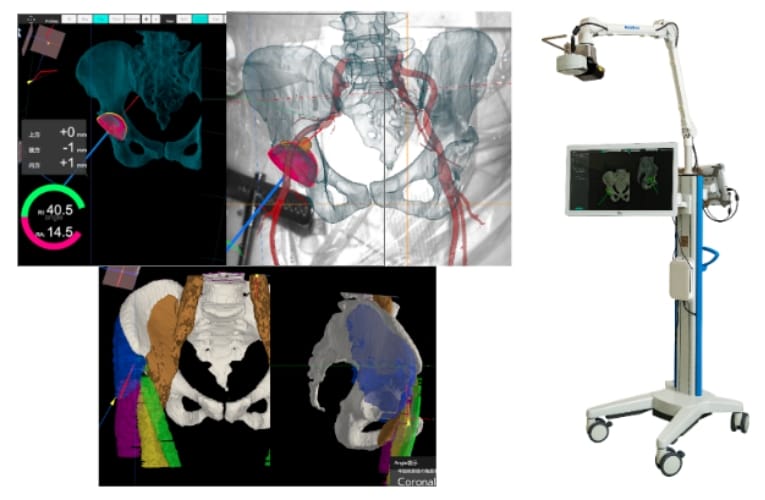

関節班では、コンピューター支援技術を積極的に活用し、安全性が高く、低侵襲かつ高精度な人工股関節置換術や人工膝関節置換術を実施しています。特に、当院独自に開発した拡張現実(Augmented Reality, AR)技術を取り入れたナビゲーションシステムを導入することで、より正確な手術を実現しています。この技術により、血管や筋肉を詳細に描出することが可能となり、さらなる安全性の向上に貢献しています。また、ロボット支援手術も取り入れており、これら最先端のデジタル技術によって、精密で個別化された医療を提供し、患者さまの満足度向上を目指しています。

ARナビゲーションを用いることで、人工股関節の正確な設置が可能となり、

さらに筋肉や血管を可視化することで、安全性の高い手術が実現します。

さらに、ロボット支援技術も取り入れることで、

より正確で患者満足度の高い手術を目指しています